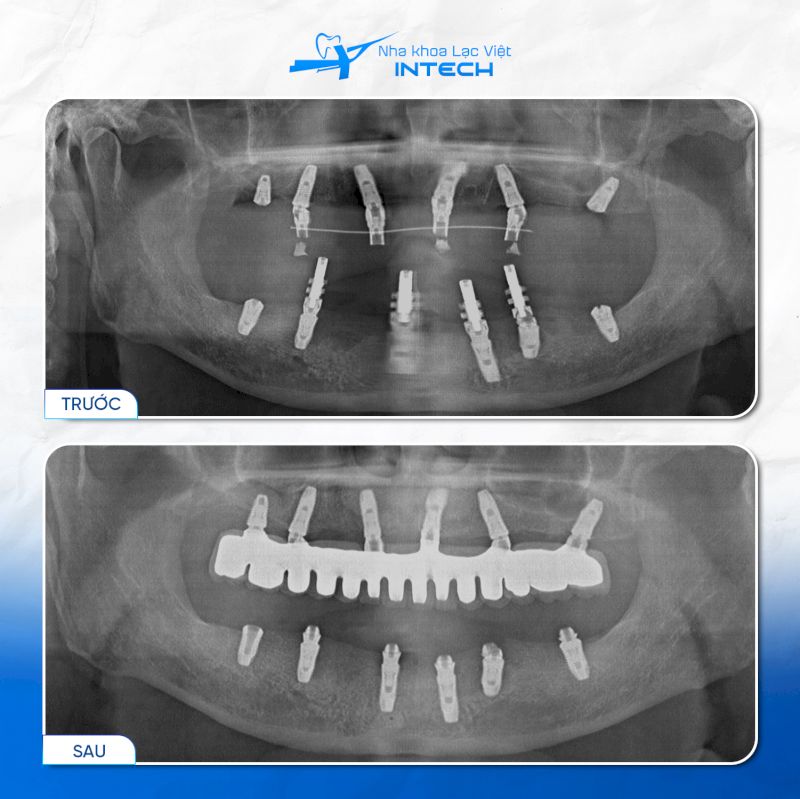

Theo nghiên cứu của Giáo sư Per-Ingvar Branemark (1965), ông đã thực hiện ca cấy ghép Implant nha khoa đầu tiên bằng Titanium trên một bệnh nhân mất răng toàn bộ, giúp bệnh nhân phục hồi chức năng ăn nhai. Đây được coi là cột mốc quan trọng trong lĩnh vực cấy ghép nha khoa, đánh dấu lần đầu tiên khái niệm tích hợp xương (osseointegration) được áp dụng trên người.

Đến năm 1986, Giáo sư Branemark và các cộng sự công bố kết quả thí nghiệm trên tạp chí khoa học Acta Orthop. Kết quả thực nghiệm cho thấy Implant Titanium tạo liên kết sinh học vững chắc với xương hàm và tồn tại vững ổn trong hơn 20 năm.